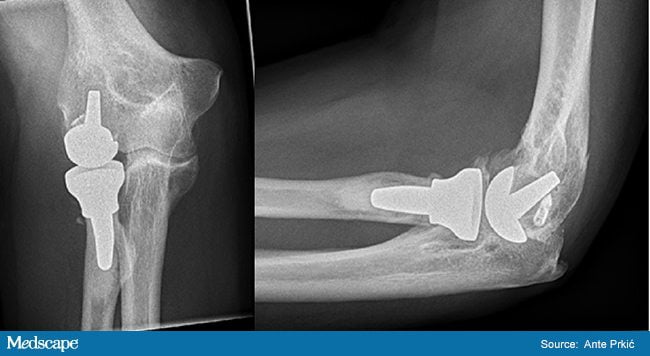

Эндопротезирование локтевого сустава

Установка искусственного сустава проводится под эндотрахеальным наркозом. Хирург делает разрез на задней поверхности локтя, отделяет и закрепляет нерв, рассекает фасции, сухожилия. После удаления локтевого отростка устанавливает имплантат, закрепляет его цементным или бесцементным способом.

Затем хирург фиксирует локтевой нерв в отдельном канале, сшивает мягкие ткани. Реабилитация начинается спустя 1-2 дня. Срок службы эндопротеза — 10-15 лет.